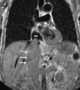

Local tumor extension